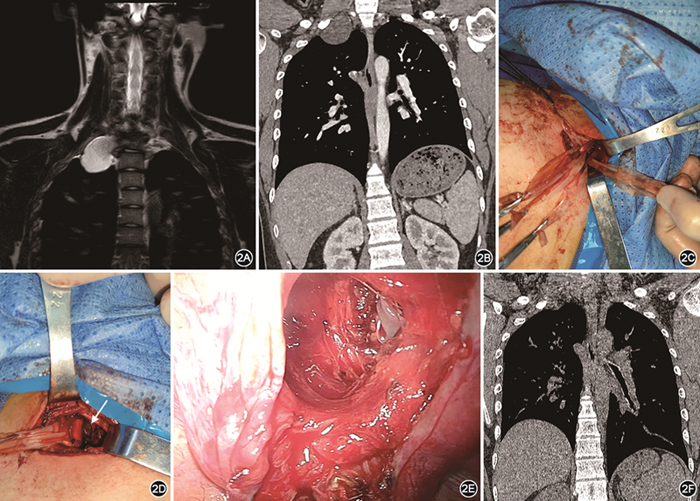

患者2 男性,17岁,主因“右上肢麻木伴乏力进行性加重3个月”于2021年12月13日入上海市肺科医院,患者曾于外院诊断为“右侧T1椎间孔哑铃状占位,考虑为神经鞘瘤,椎管内部分压迫脊髓”。经影像科、骨科、胸外科、手外科多学科诊疗团队讨论,决定分期手术。于2021年8月19日在全身麻醉下行后方入路椎管内占位切除,术后病理学检查证实为神经鞘瘤,术中旷置椎间孔外胸顶部分肿瘤。术后患者右上肢麻木乏力症状明显改善,术后4个月住胸外科拟二期手术切除剩余部分肿瘤。体检:右上肢肌力和感觉正常。实验室检查无明显异常。MRI提示右侧T1椎间孔扩大,右侧脊柱旁神经鞘瘤,最大径约5 cm,占据右侧胸廓出口(图2A);CT示肿瘤位于颈胸交界处(图2B)。于2021年12月16日行锁骨上切口联合单孔胸腔镜胸顶肿瘤切除术。与患者1采用同样方法,先于右侧锁骨上方行长6 cm切口,游离锁骨下动静脉和C5~8神经根,分别予橡胶带牵拉暴露。颈部操作以锐性配合钝性分离为主,逐一解剖游离各神经血管,期间所有能量操作采用双极电凝,电凝时间不宜过长,以免电传导造成神经损伤。待所有神经根以及血管游离牵拉后,钝性分离肿瘤上极,将肿瘤向下进一步压入胸腔,采用右侧腋中线第4肋间单孔胸腔镜以钝性游离为主配合能量器械,游离肿瘤胸腔内部分后经胸腔切口取出(图2C~2E)。胸腔引流管1根自单孔切口引出,颈部切口一期皮内缝合不放置引流。颈部游离操作时间1.0 h,单孔胸腔镜切除肿瘤时间0.5 h,术中出血量10 ml。术后第1天复查胸部X线片肺复张良好,拔除引流管,术后第2天出院。术后主诉右手掌小指、无名指、中指尺侧麻木及感觉异常,2周后恢复。术后1个月随访,切口愈合良好,CT检查结果示胸顶少量胸膜增厚粘连(图2F)。